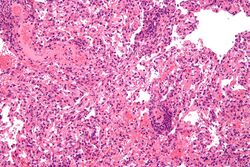

Lung transplant rejection

Deontological issues are issues about whether a person has an ethical duty or responsibility to take an action. Nearly all scholars and societies around the world agree that voluntarily donating organs to sick people is ethically permissible. Although nearly all scholars encourage organ donation, fewer scholars believe that all people are ethically required to donate their organs after death. Similarly, nearly all religions support voluntary organ donation as a charitable act of great benefit to the community. Certain small faiths such as Jehovah Witnesses and Shinto are opposed to organ donation based upon religious teachings; for Jehovah Witnesses this opposition is absolute whereas there exists increasing flexibility amongst Shinto scholars. The Roma People, are also often opposed to organ donation based on prevailing spiritual beliefs and not religious views per se.[130] Issues surrounding patient autonomy, living wills, and guardianship make it nearly impossible for involuntary organ donation to occur.